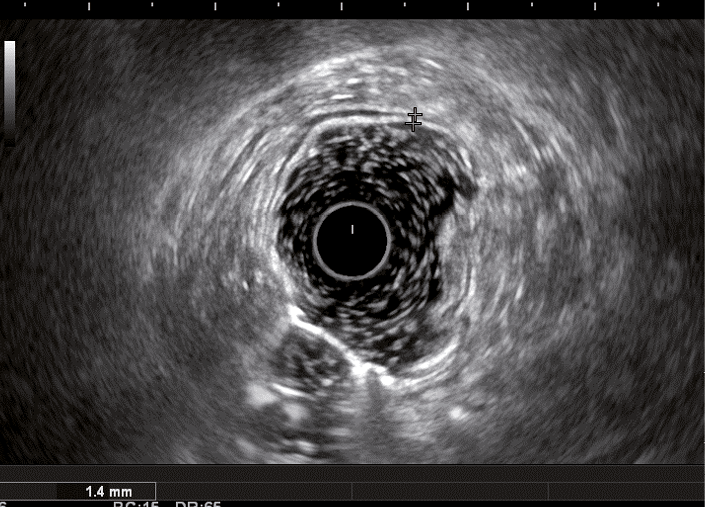

Рис. 4. Эндосонографическая картина толстой кишки при болезни Крона; 1 – отсутствие дифференцировки слоев кишечной стенки; 2 – утолщение стенки толстой кишки за счет всех слоев

Кишечная стенка статистически значимо чаще утолщалась за счет слизисто-подслизистого слоя при ЯК, чем при БК: в 82 и 7,14% соответственно; диагностическая чувствительность данного признака была 82%, а специфичность – 93% (табл. 1). При БК изменение стенки толстой кишки за счет трансмурального утолщения выявлялось статистически значимо чаще (68%), чем при ЯК (9%) (чувствительность 68%, специфичность 91%). Статистически значимых различий в частоте изменений мышечного слоя кишки отмечено не было. Только при БК в 68% случаев отсутствовала дифференцировка слоев кишечной стенки в фазе обострения (чувствительность и специфичность признака составили 68 и 100% соответственно) (см. рис. 4). При ЯК на фоне «смазанности» слизисто-подслизистого слоя у всех больных можно было визуализировать мышечный и серозный слои (см. табл. 1, рис. 3).